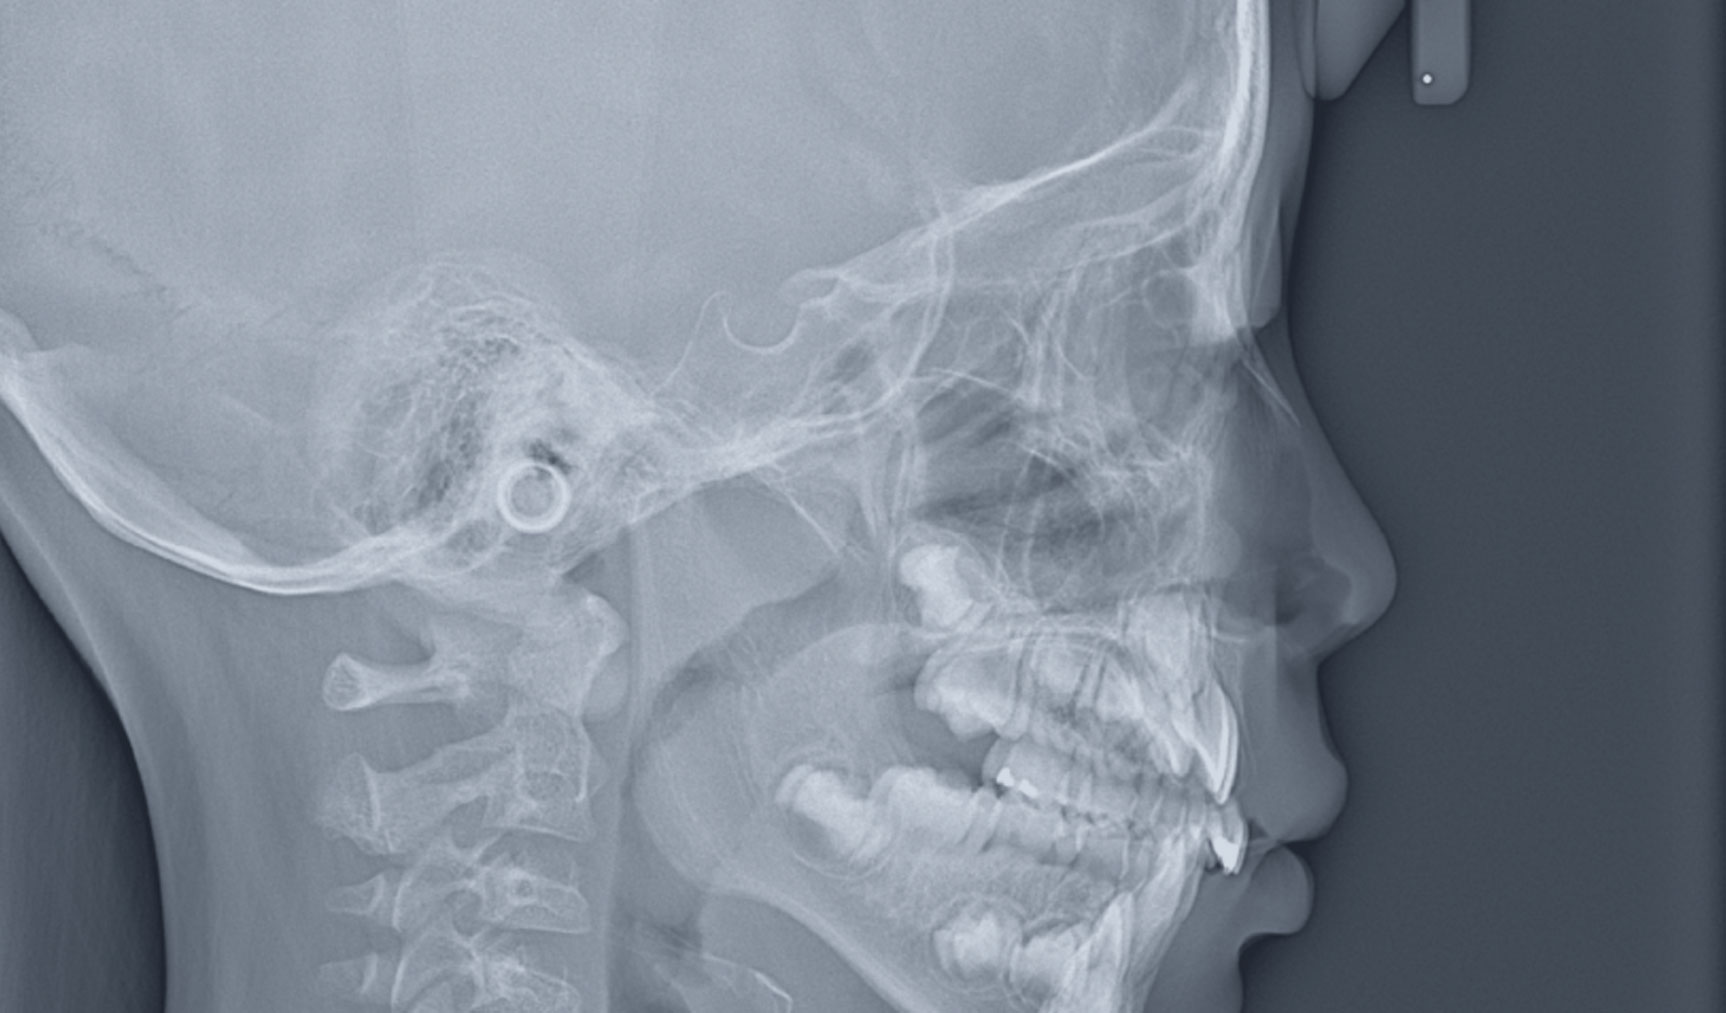

駒沢よしや矯正歯科では、精密検査の一環として頭部エックス線写真(セファログラム)を撮影しています。この検査は、顎や歯の状態を立体的かつ詳細に把握するために欠かせない重要なステップです。

6 頭部エックス線写真(セファログラム)

セファログラムとは?

セファログラムとは、頭部全体を横から撮影する特殊なエックス線写真です。これにより、以下のような情報を得ることができます。

顎の位置関係の分析

上下の顎骨のバランスや位置を確認します。

歯列と顔面の骨格の関係

歯並びが顔の骨格とどのように調和しているかを分析します。

治療計画の精度向上

患者さま一人ひとりに合わせた矯正治療計画を立てる際に役立ちます。

セファログラムの役割

正確な診断

セファログラムは、目に見えない骨格や咬み合わせの問題を正確に診断するために使用されます。

治療効果の測定

治療前後で撮影することで、矯正治療がどれだけ効果を上げているかを科学的に評価できます。

将来の成長予測

特にお子さまの場合、成長に伴う顎や歯の変化を予測し、治療タイミングを見極めます。

快適な撮影環境

駒沢よしや矯正歯科では、エックス線撮影機器を導入し、短時間での撮影が可能です。また、放射線の被ばく量を抑えた安全な撮影を心がけています。

セファログラムが必要な理由

矯正治療は、歯並びだけでなく顔全体のバランスを考慮して進めるものです。そのため、セファログラムは治療の基盤となる大切な情報を提供します。